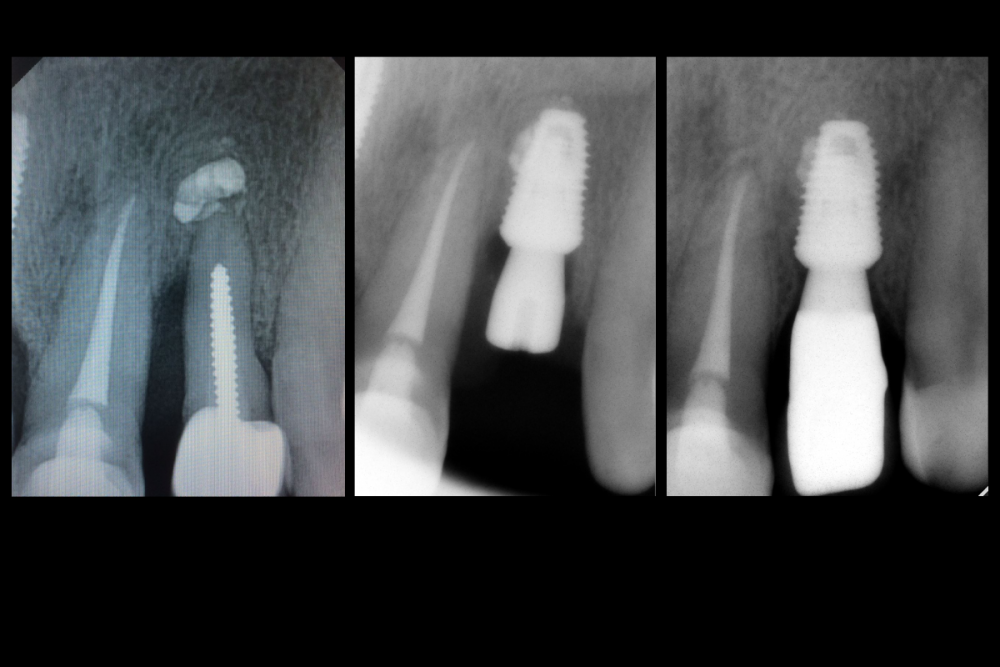

Карен Аванесов Опубликовано 7 декабря, 2021 Автор Поделиться Опубликовано 7 декабря, 2021 Результат 2 Ссылка на комментарий

Карен Аванесов Опубликовано 7 декабря, 2021 Автор Поделиться Опубликовано 7 декабря, 2021 Не нравится мне состояние периапикальных тканей у центрального резца, жалоб у пациента нет, но что то не нравится мне. Грешу на то, что он между двумя имплантатами, но, контакты физиологичны, без сдавливания. Ссылка на комментарий

Fin Опубликовано 7 декабря, 2021 Поделиться Опубликовано 7 декабря, 2021 (изменено) 5 минут назад, Карен Аванесов сказал: Результат Имплант похож на 4,5 х 8, бкз графта т.к. когда ставили щель между импл. и вестибулярной стенкой была меньше 1мм? Изменено 7 декабря, 2021 пользователем Fin Ссылка на комментарий

Fin Опубликовано 7 декабря, 2021 Поделиться Опубликовано 7 декабря, 2021 5 минут назад, Карен Аванесов сказал: Не нравится мне состояние периапикальных тканей у центрального резца, жалоб у пациента нет, но что то не нравится мне. Грешу на то, что он между двумя имплантатами, но, контакты физиологичны, без сдавливания. На втором снимке кажется, что уже есть изменения в периодонте резца. Ссылка на комментарий